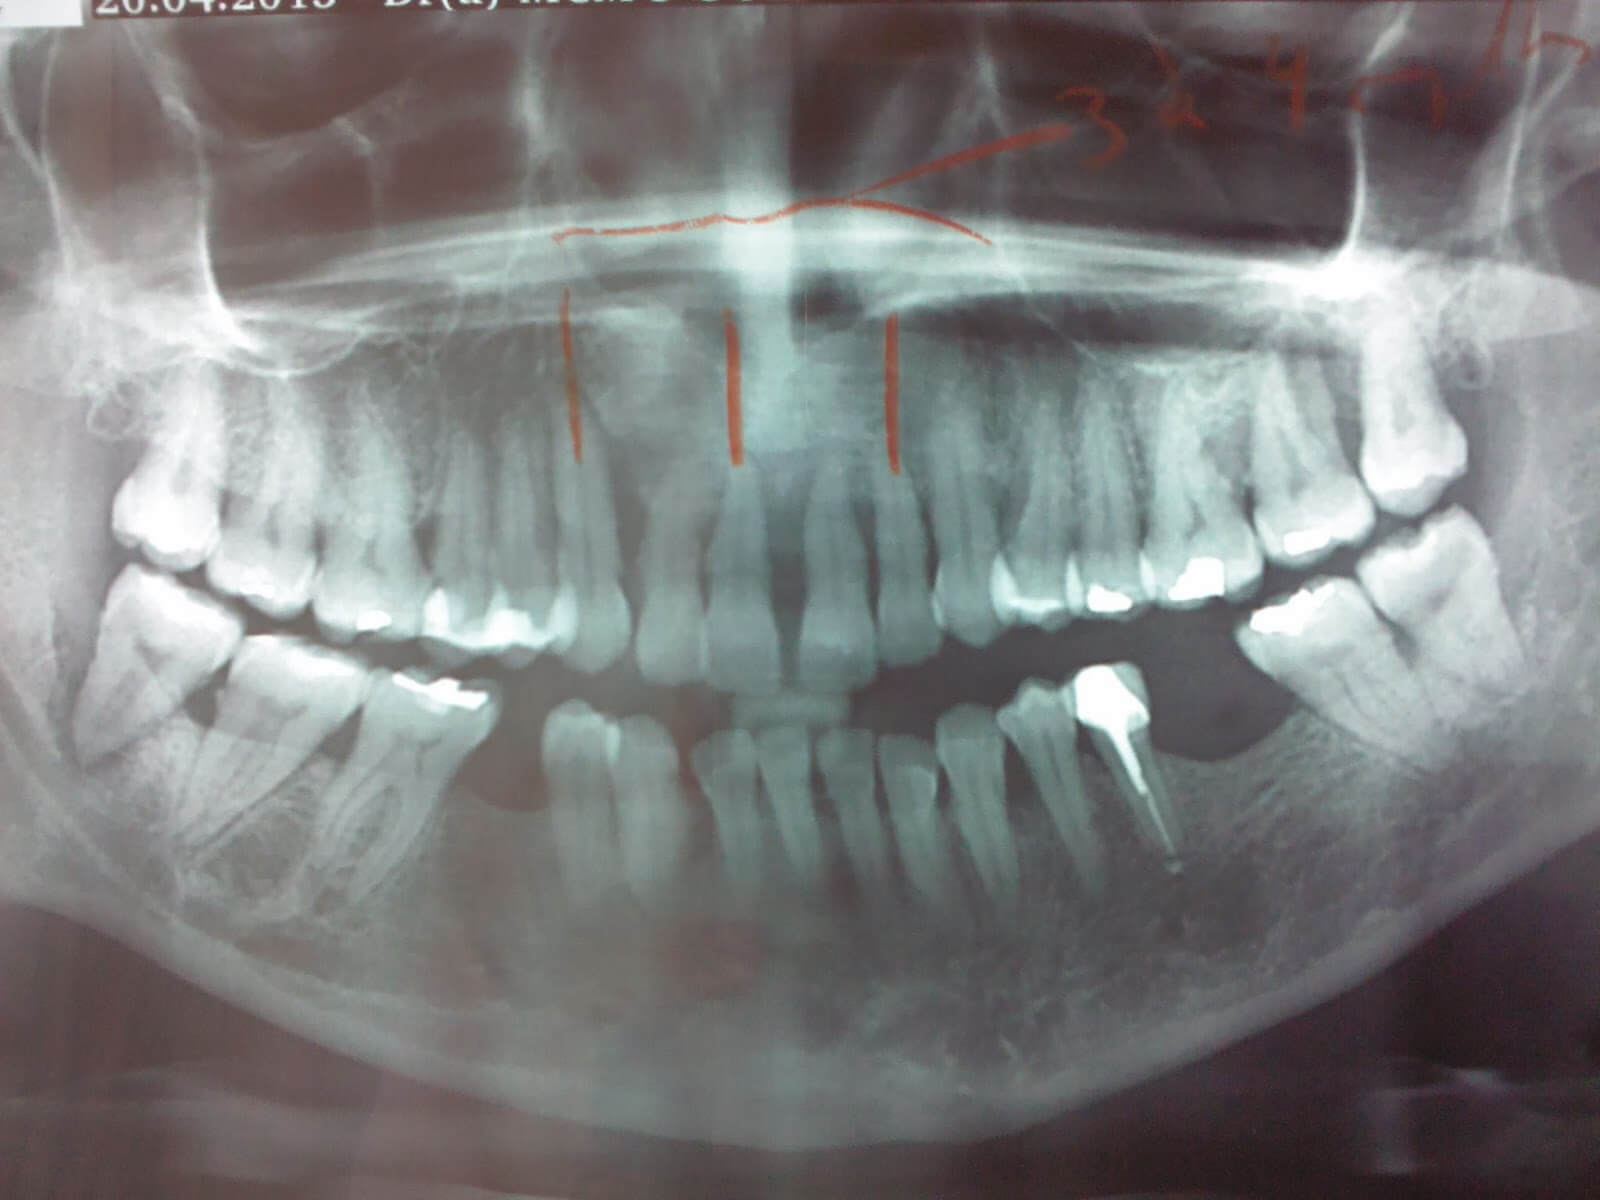

يمكنك أن تعرف افضل شكل للاسنان باشعة بانوراما ، حيث تُعرف بانوراما الأسنان أو الأشعة السينية البانورامية بأنها أشعة سينية ليتم استخدامها ليُأخَذ عن طريقها صُورًا كاملة للوجه بما في ذلك الفك بالكامل، وجميع الأسنان و أيضا الهياكل المحيطة بها، ويتمكن أطباء الأسنان في مركز الشروق للأشعة والتحاليل استنادا على تلك الصور من رؤية موقع الأعصاب الاساسي، والجيوب الأنفية، والأسنان النامية، وغيرها من الأمراض التي ترتبطها نفس العلاقة، كما يمكنهم النظر إلى مفصل الفك وعظام الفم، وتعكِس صورة الأشعة السينية البانورامية مدى صحة الفم وسلامته.

الاشعة السينية البانورامية أو ما يعرف بالتصوير الشعاعي البانورامي هو فحص باستخدام الأشعة السينية ثنائي الأبعاد للأسنان، يلتقط صورة كاملة للفم، بما في ذلك، الأسنان كلها والفكين العلوي والسفلي بالإضافة إلى الأنسجة المحيطة.

أشعة بانوراما للأسنان هي فحص منتشر يتم إجراؤه من قبل جراحي الفم و أطباء الأسنان ، فهو أداة تشخيصية ضرورية ، وذلك لأنه يقدم معلومات قيمة حول الجيوب الأنفية الفكية ووضع الأسنان وتشوهات عظام الفك و الحالة الصحية للاسنان لتحصل علي افضل شكل للاسنان باشعة بانوراما، وتستخدم تلك الأشعة أيضًا لتخطيط مراحل العلاج قبل وضع أطقم الأسنان الكاملة والجزئية والتقويم والخلع ووضع الغرسات وهي زراعة الأسنان .

للحصول على افضل شكل للاسنان باشعة بانوراما فالأشعة البانورامية تقوم بانتاج صورة مسطحة وتقدم تفاصيل عن الاسنان و العظام .

وتوفر أشعة بانوراما الأسنان تقييم مبدئي لحالة الاسنان و الفك والعظام المحيطة، وإذا اكتشف الطبيب أي اضطراب في الفك أو الأسنان فيمكن أن يطلب إجراء فحوصات أكثر دقة وتفصيل مثل استخدام أشعة الرنين المغناطيسي.

ان الأشعة السينية البانورامية تقدم لطبيب الأسنان فرصة لرؤية ثنائية الأبعاد من الأذن إلى الأذن و للفكين العلوي والسفلي، وتتكون المعدات الضرورية للتصوير من ذراع دوار يحتوي علي مولد الأشعة السينية، وأيضا فيلم مرفق متحرك لتحميل الصور، وبعد ذلك يطلب من الحاله أن توضع رأسه بين هذين الجهازين، و اثناء اجراء الاشعه يتحرك مولد الأشعة السينية بشكل دائري حول الرأس ويلتقط الصور بشكل متعامد بقدر المستطاع ، ثم تُحدد وضعية كلًا من الرأس والجسم مدى حدة وبروز ،وفائدة الأشعة السينية لطبيب الأسنان، كما يتم تكبير الصور بنسبة يمكن أن تصل إلى 30% وذلك لينم ضمان تسجيل أدق التفاصيل.

3. التصوير البانورامي :

التصوير البانورامي يمزج تقنية مختلفة قليلًا، وعن طريقه يحلق جهاز التصوير حول رأس المريض لعدة ثوان وفي النهاية يتم الحصول على صورة تمثل كلا الفكين، بالإضافة إلى تجاويف حجر الأنف، ومباني أخرى مجاورة، مثل: قناة عصب الفك السفلي.

يعتبر هذا التصوير أقل دقة، ويتم تنفيذه غالبا قبل العملية المعقدة الخاصة بقلع السن ، أو زرع الأسنان، أو الحاجة إلى تشخيص الأمراض والأورام.